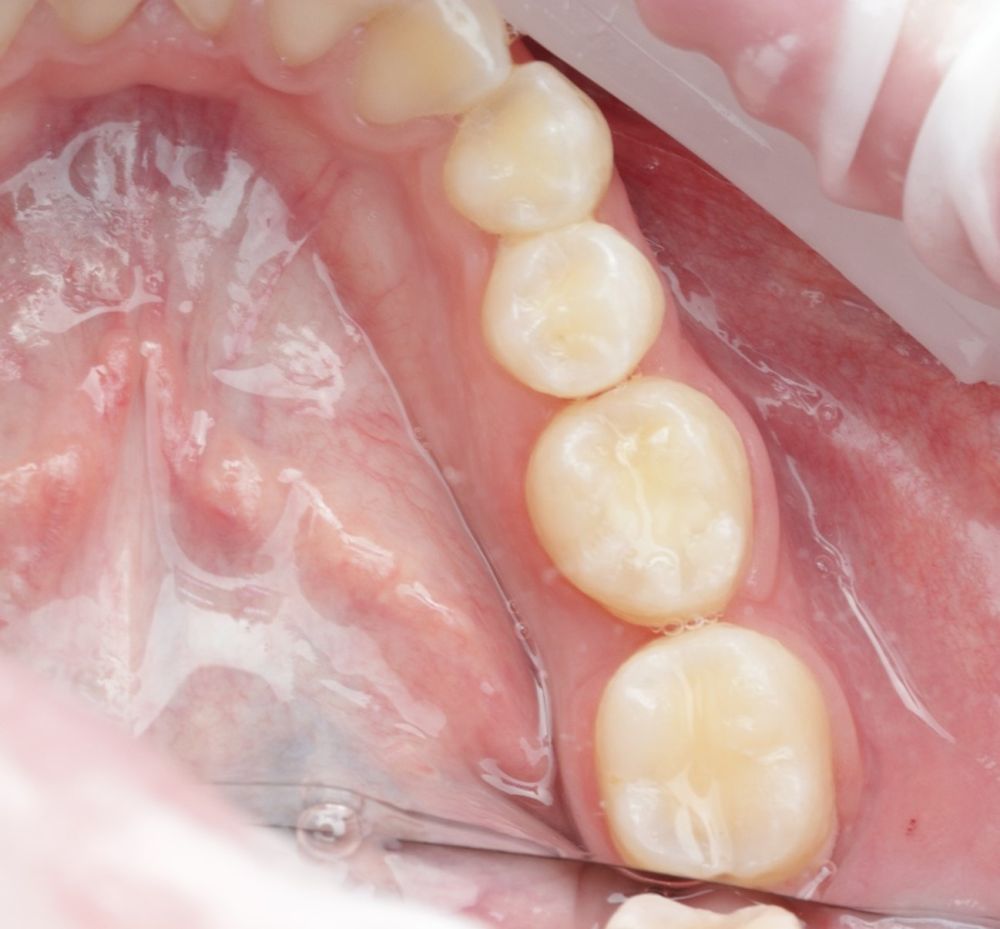

Se reporta el caso de un autotrasplante del tercer molar inferior derecho al alveolo postextracción de un primer molar inferior, en una paciente de 22 años de edad. Actualmente, el autotransplante se considera una opción de tratamiento si se siguen los criterios de selección del caso adecuados, y se realiza una técnica quirúrgica protocolizada. El diagnóstico planificado mediante CBCT, la simulación virtual y la confección de una réplica en 3D optimiza la técnica de forma segura, predecible con tiempos de cirugía menores.

Las tasas de éxito de la técnica se han registrado hasta un 90% entre los 3 y 5 años de seguimiento4,10,12.

Todo ello favorece un crecimiento esquelético continuo y resistencia a las cargas oclusales8,12.